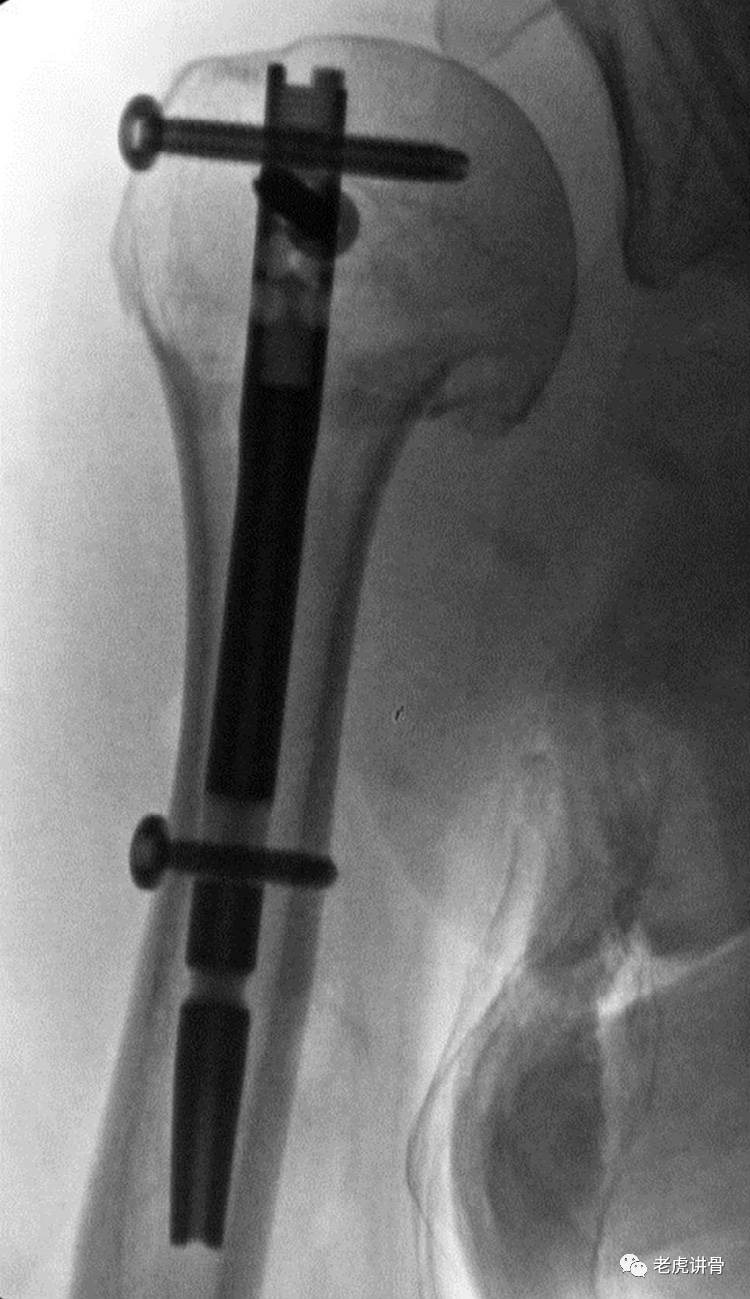

图3 髓内钉固定肱骨外科颈骨折后最终的前后位X线显示存在轻度的过度复位,肱骨头-颈关系得到完美重建。重点是避免骨折内翻和骨折分离。